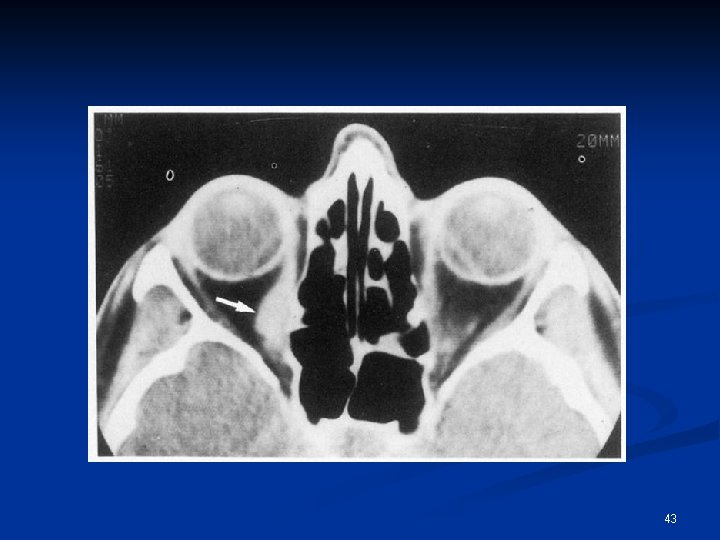

Examens radiologiques n n n Scanner orbitaire et massif facial, sans et avec injection, dans les 3 plans IRM, sans et avec injection, dans les 3 plans Echographie oculaire Artériographie Dacrocystographie, Dacryoscanner 42

43